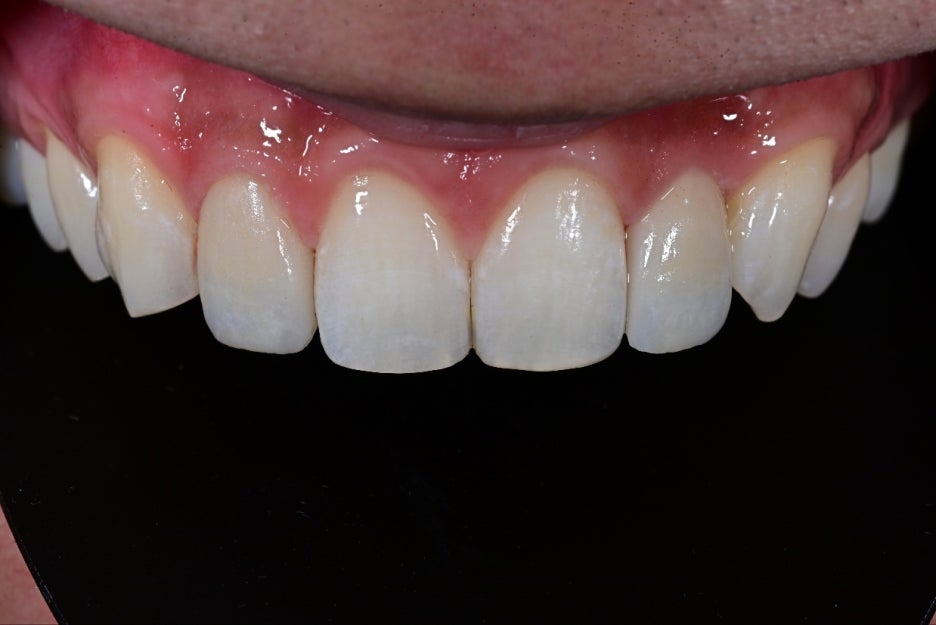

<After bonding>

Object Zero Laminate

Right after placement, the patient said,

It looks so natural, as if they were my original teeth, and not obvious at all.

They were very satisfied.